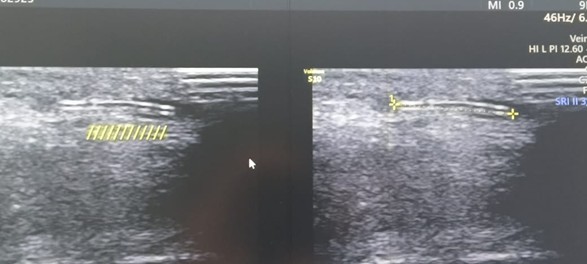

Radiology: An urgent Upper Limb (UL) Doppler Ultrasound was requested to localize the retained foreign body and assess vascular integrity. Although a separate formal Doppler report is not available in the documentation, operative notes confirm that the migration and location of the IV cannula tip were verified using ultrasound guidance.

Under aseptic precautions, a skin incision was made over the presumed site. Utilizing ultrasound (USG) guidance, the cephalic vein was identified, and the migration of the IV cannula tip was confirmed. The vein was exposed, and a venotomy (incision into the vein) was performed. The cannula fragment was successfully removed. No intraoperative complications were documented. Post-removal confirmation was achieved via USG to reconfirm the absence of residual fragments. The venotomy and wound were closed.

The immediate localization using clinical findings and subsequent confirmation via Upper Limb Doppler Ultrasound was critical. Utilizing USG guidance intraoperatively further enhanced the precision of the venotomy and confirmed the successful removal of the fragment, minimizing trauma to the vascular structures. The use of Local Anaesthesia with mild sedation was advantageous, promoting rapid recovery compared to general anaesthesia.